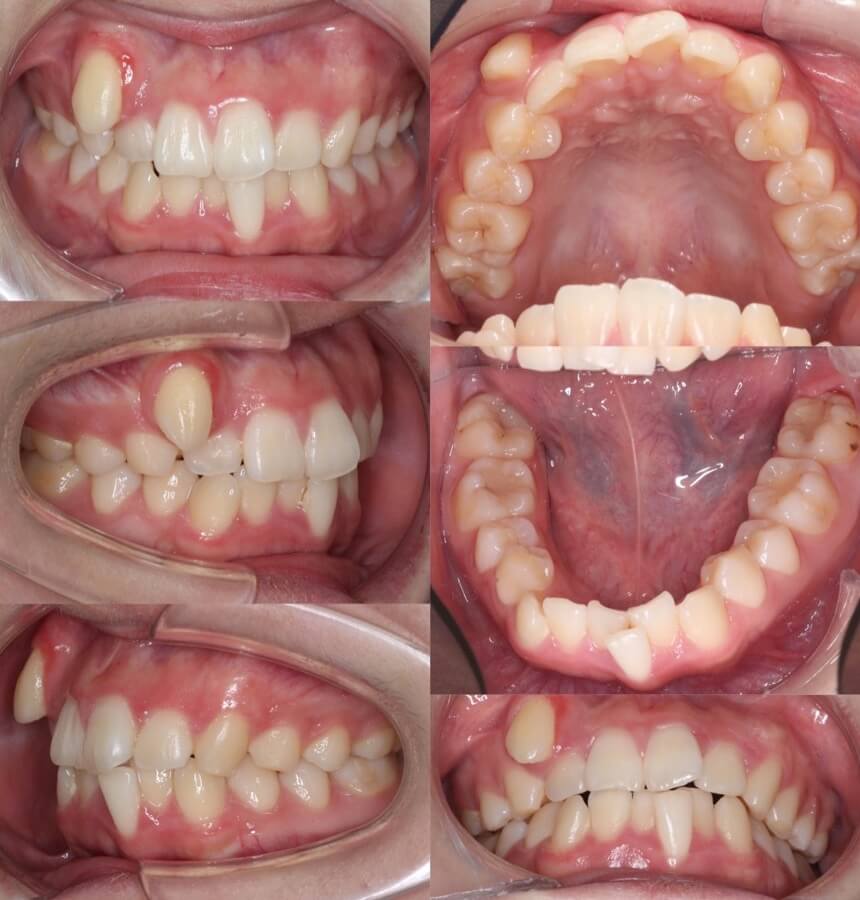

大学生女性・軽度叢生・マウスピース型装置

顎が前後に長いタイプであったため、上下の親知らずは抜歯せず、少し横方向に拡大もしながら並べました。

<症例概要> 難易度★★☆☆☆

主訴:前歯のふぞろい

年齢・性別:大学生女性

住まい:千葉県八千代市

症状:叢生・臼歯関係III級

治療方針:下顎後方移動・拡大・IPR

抜歯:上左右4番(計2本)

治療装置:マウスピース型矯正装置(アライナー装置)

治療期間:1年8か月

アライナー枚数:54+27ステージ

リテーナー:上下フィックスタイプ+クリアタイプ

治療費用:990,000(税込)

代表的副作用:痛み・治療後の後戻り・歯根吸収・歯髄壊死・歯肉退縮

▶︎その他の副作用

下顎歯列の拡大と遠心移動にIPRを加え、外にはみ出している犬歯を中にいれていきました。